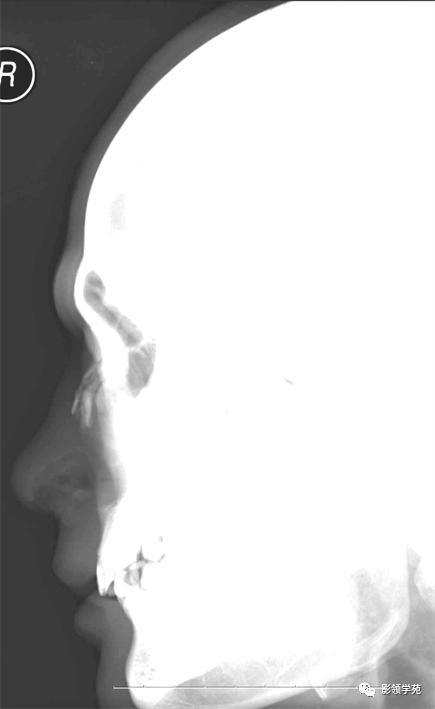

X线平片:侧位

鼻骨正常侧位